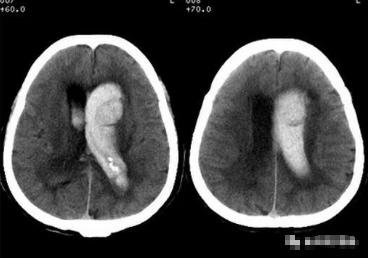

一、内囊出血:

是最常见的出血部位。其典型临床表现为对侧"三偏"(偏瘫、偏身感觉障碍、偏盲)。内囊出血范围较大,神经损害症状较重。但若出血偏于内囊外侧,主要损害外囊部位,则临床症状多较轻些,多无意识障碍,偏瘫也轻,预后较好。

左侧基底节区较大范围高密度影,边界清晰,周围可见低密度水肿,左侧侧脑脑室消失闭塞,中线结构右移。